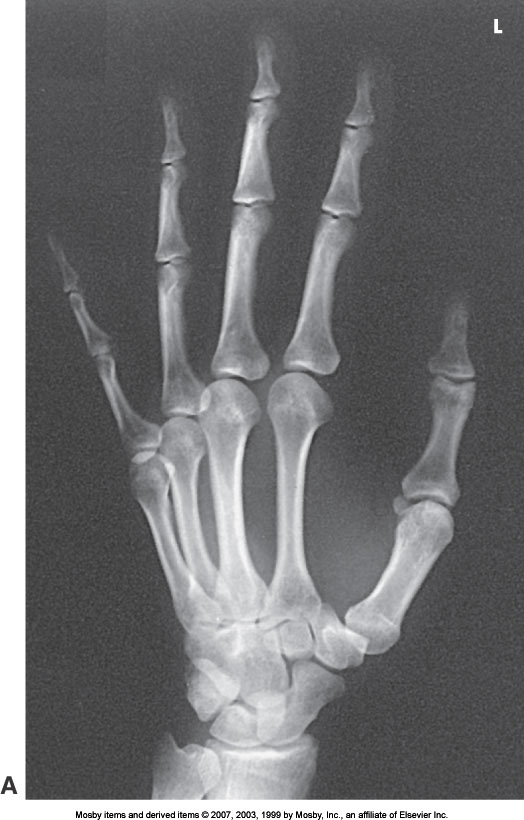

PA Oblique Hand

What position is demonstrated?